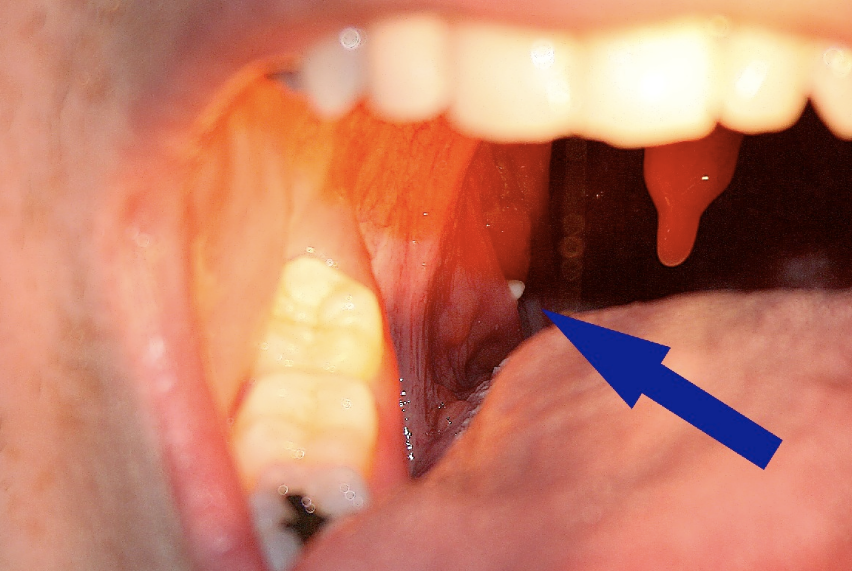

A tonsillolith protrudes from the tonsil